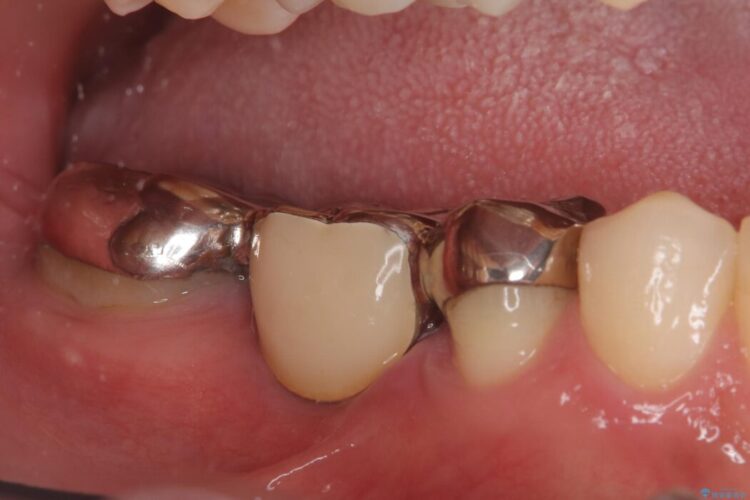

右下奥歯の5・6・7番に装着されていたブリッジの不具合を主訴にご来院された患者様です。

ブリッジを外し、欠損している6番にインプラントを埋入。土台となっていた5番と7番は、セラミッククラウンで修復。